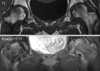

Fig. 1

A 28-yr-old woman with pain in both hips, which occurred at gestation 32 weeks in the left hip and immediately after delivery in the right. Anteroposterior radiograph obtained 1 week postpartum shows marked osteopenia in both proximal femurs.